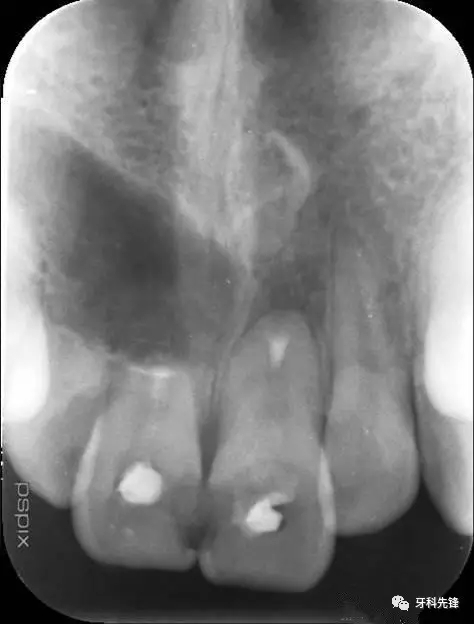

圖1.術(shù)前的根尖片影像:12、11根尖2/3壓迫吸收、11、21根管內(nèi)各有一牙膠尖。

圖2.術(shù)前的CBCT檢查:11牙根幾乎完全吸收、12牙根吸收2/3. 21牙齒唇側(cè)牙根部分吸收。